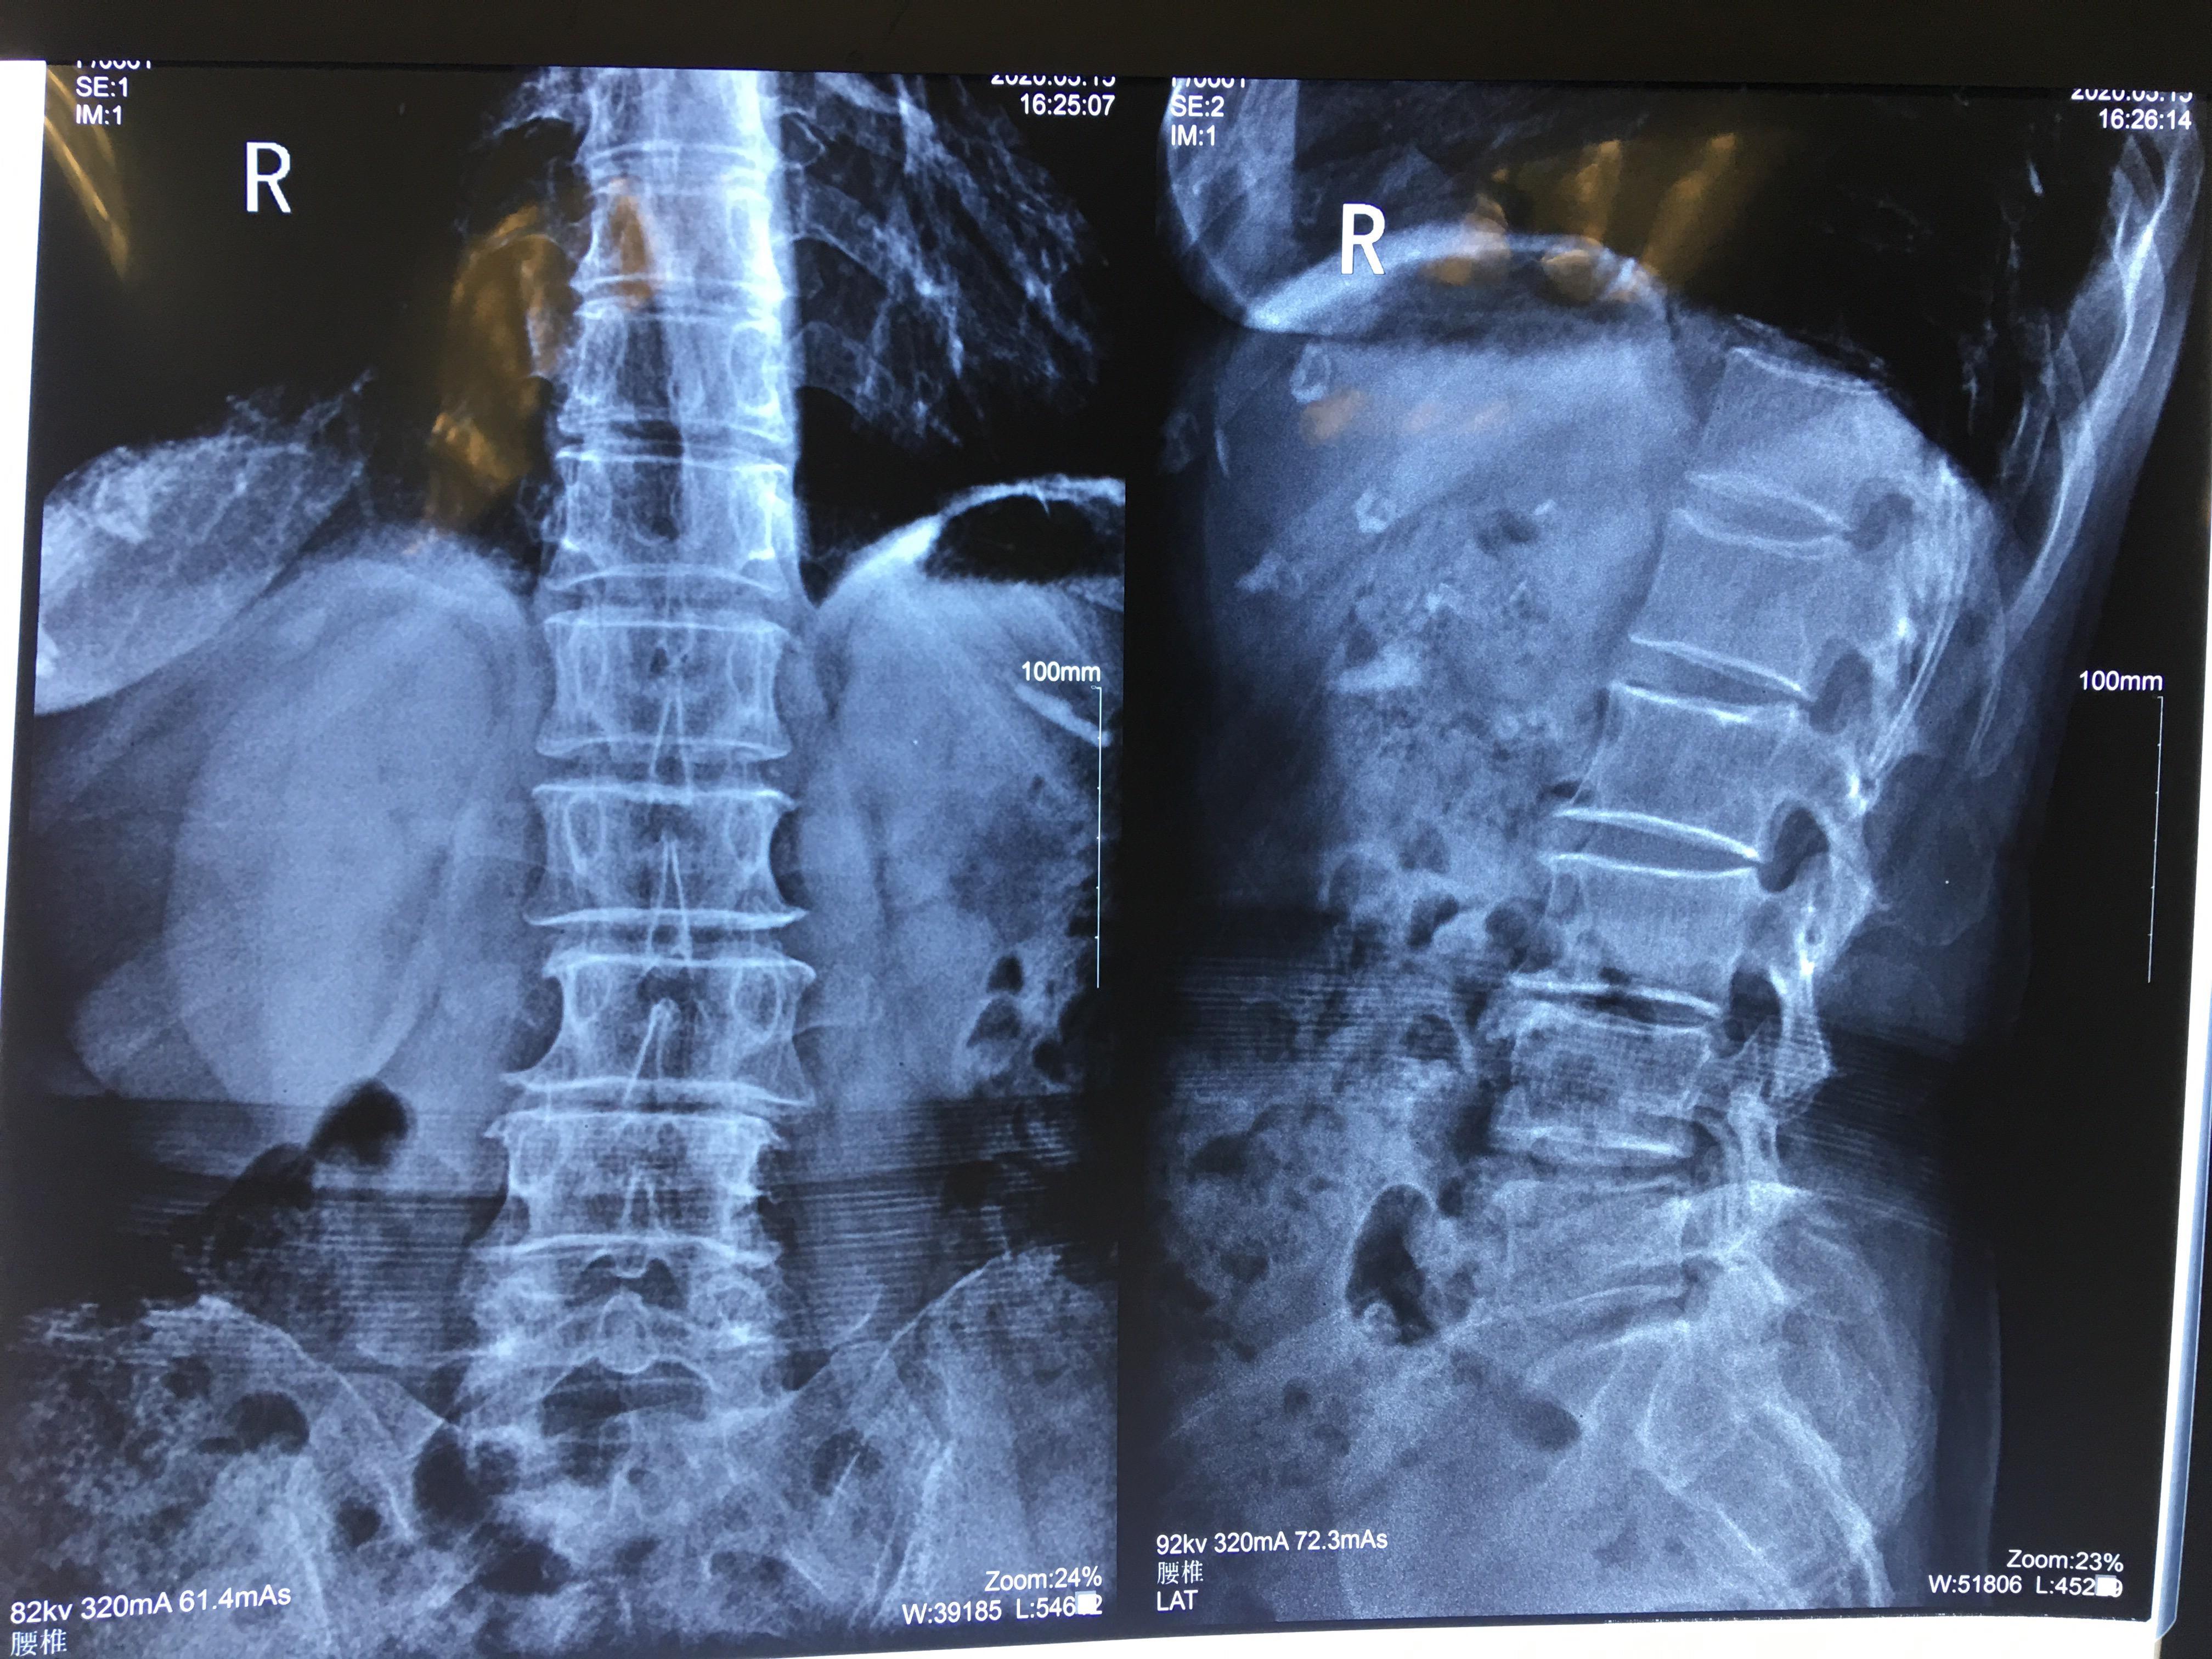

止住疼痛后家属带其检查,报告显示:腰椎骨体部L3/l4,L4/L5,L5/S1突出。

后发展到 平常站立、坐下都觉不适 ,通过医院检查:腰椎生理曲度变浅、L4/5、L5/S1椎间盘突出向四周膨出,硬膜囊略受压。